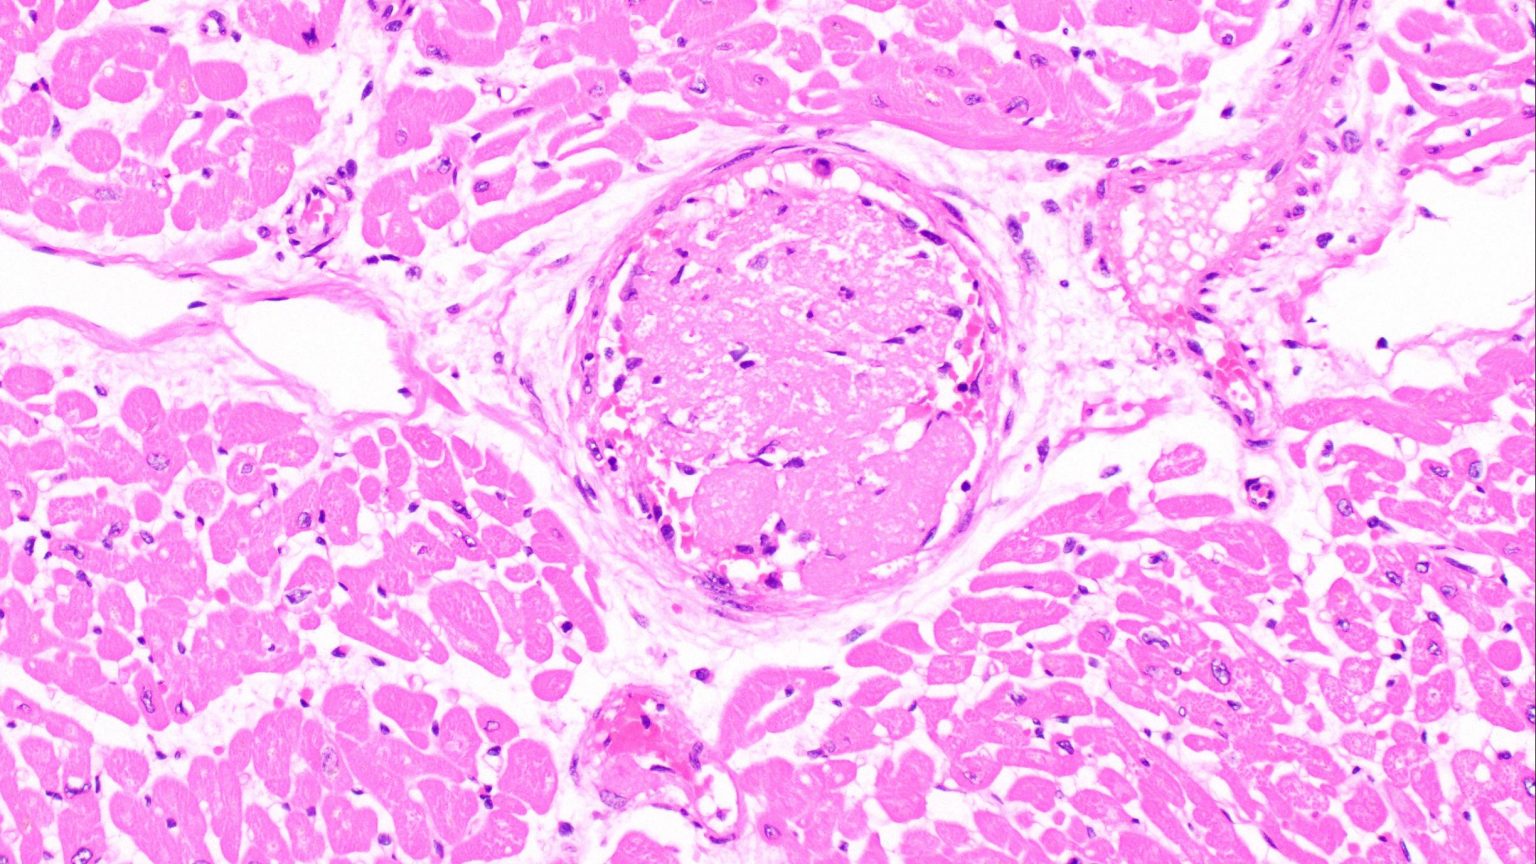

Un estudio pequeño pero detallado llevó a cabo evaluaciones post mortem en el tejido cardíaco de 15 pacientes con COVID-19, incluidos los primeros hallazgos cardíacos post mortem de tres pacientes que habían superado la infección. Se comparó a estos pacientes con un grupo de control de pacientes con gripe y otro grupo de control de pacientes que no tuvieron ninguna infección viral.

En los pacientes con COVID-19, el 33%  de los casos (activos y superados) mostró miocarditis en, al menos, alguna medida; pero el estudio no descubrió evidencia contundente del SARS-CoV-2, o virus que causa el COVID-19, en el tejido cardíaco de los pacientes estudiados.

“El estudio mostró que, a diferencia de otros virus, el COVID-19 parece ejercer un impacto sobre los vasos sanguíneos pequeños del corazón”, señala la Dra. Melanie Bois, patóloga cardiovascular de Mayo Clinic y primera autora del estudio.

Las pruebas con tinción química revelaron coágulos en los vasos sanguíneos pequeños del tejido cardíaco. Estos coágulos sanguíneos fibrosos pueden aún estar presentes incluso después de eliminado el virus, por lo que es factible que se proponga una terapia anticoagulante como tratamiento de los pacientes con COVID-19, posiblemente después de eliminado el virus.

El estudio también cita otras afecciones cardíacas subyacentes que son conocidas por su relación con peores resultados en pacientes con COVID-19. Cabe mencionar que en más del 26% de los pacientes con COVID-19 estudiados se descubrió amiloidosis cardíaca, que consiste en una acumulación cohesiva de proteínas anormales que interfiere con la capacidad de funcionamiento del corazón.

Esta tasa es muy superior a la ocurrencia del 3,7%  de amiloidosis cardíaca que normalmente ha visto Mayo Clinic en las autopsias de pacientes. El descubrimiento plantea que esta afección cardíaca subyacente puede conllevar mayor riesgo de muerte por COVID-19.